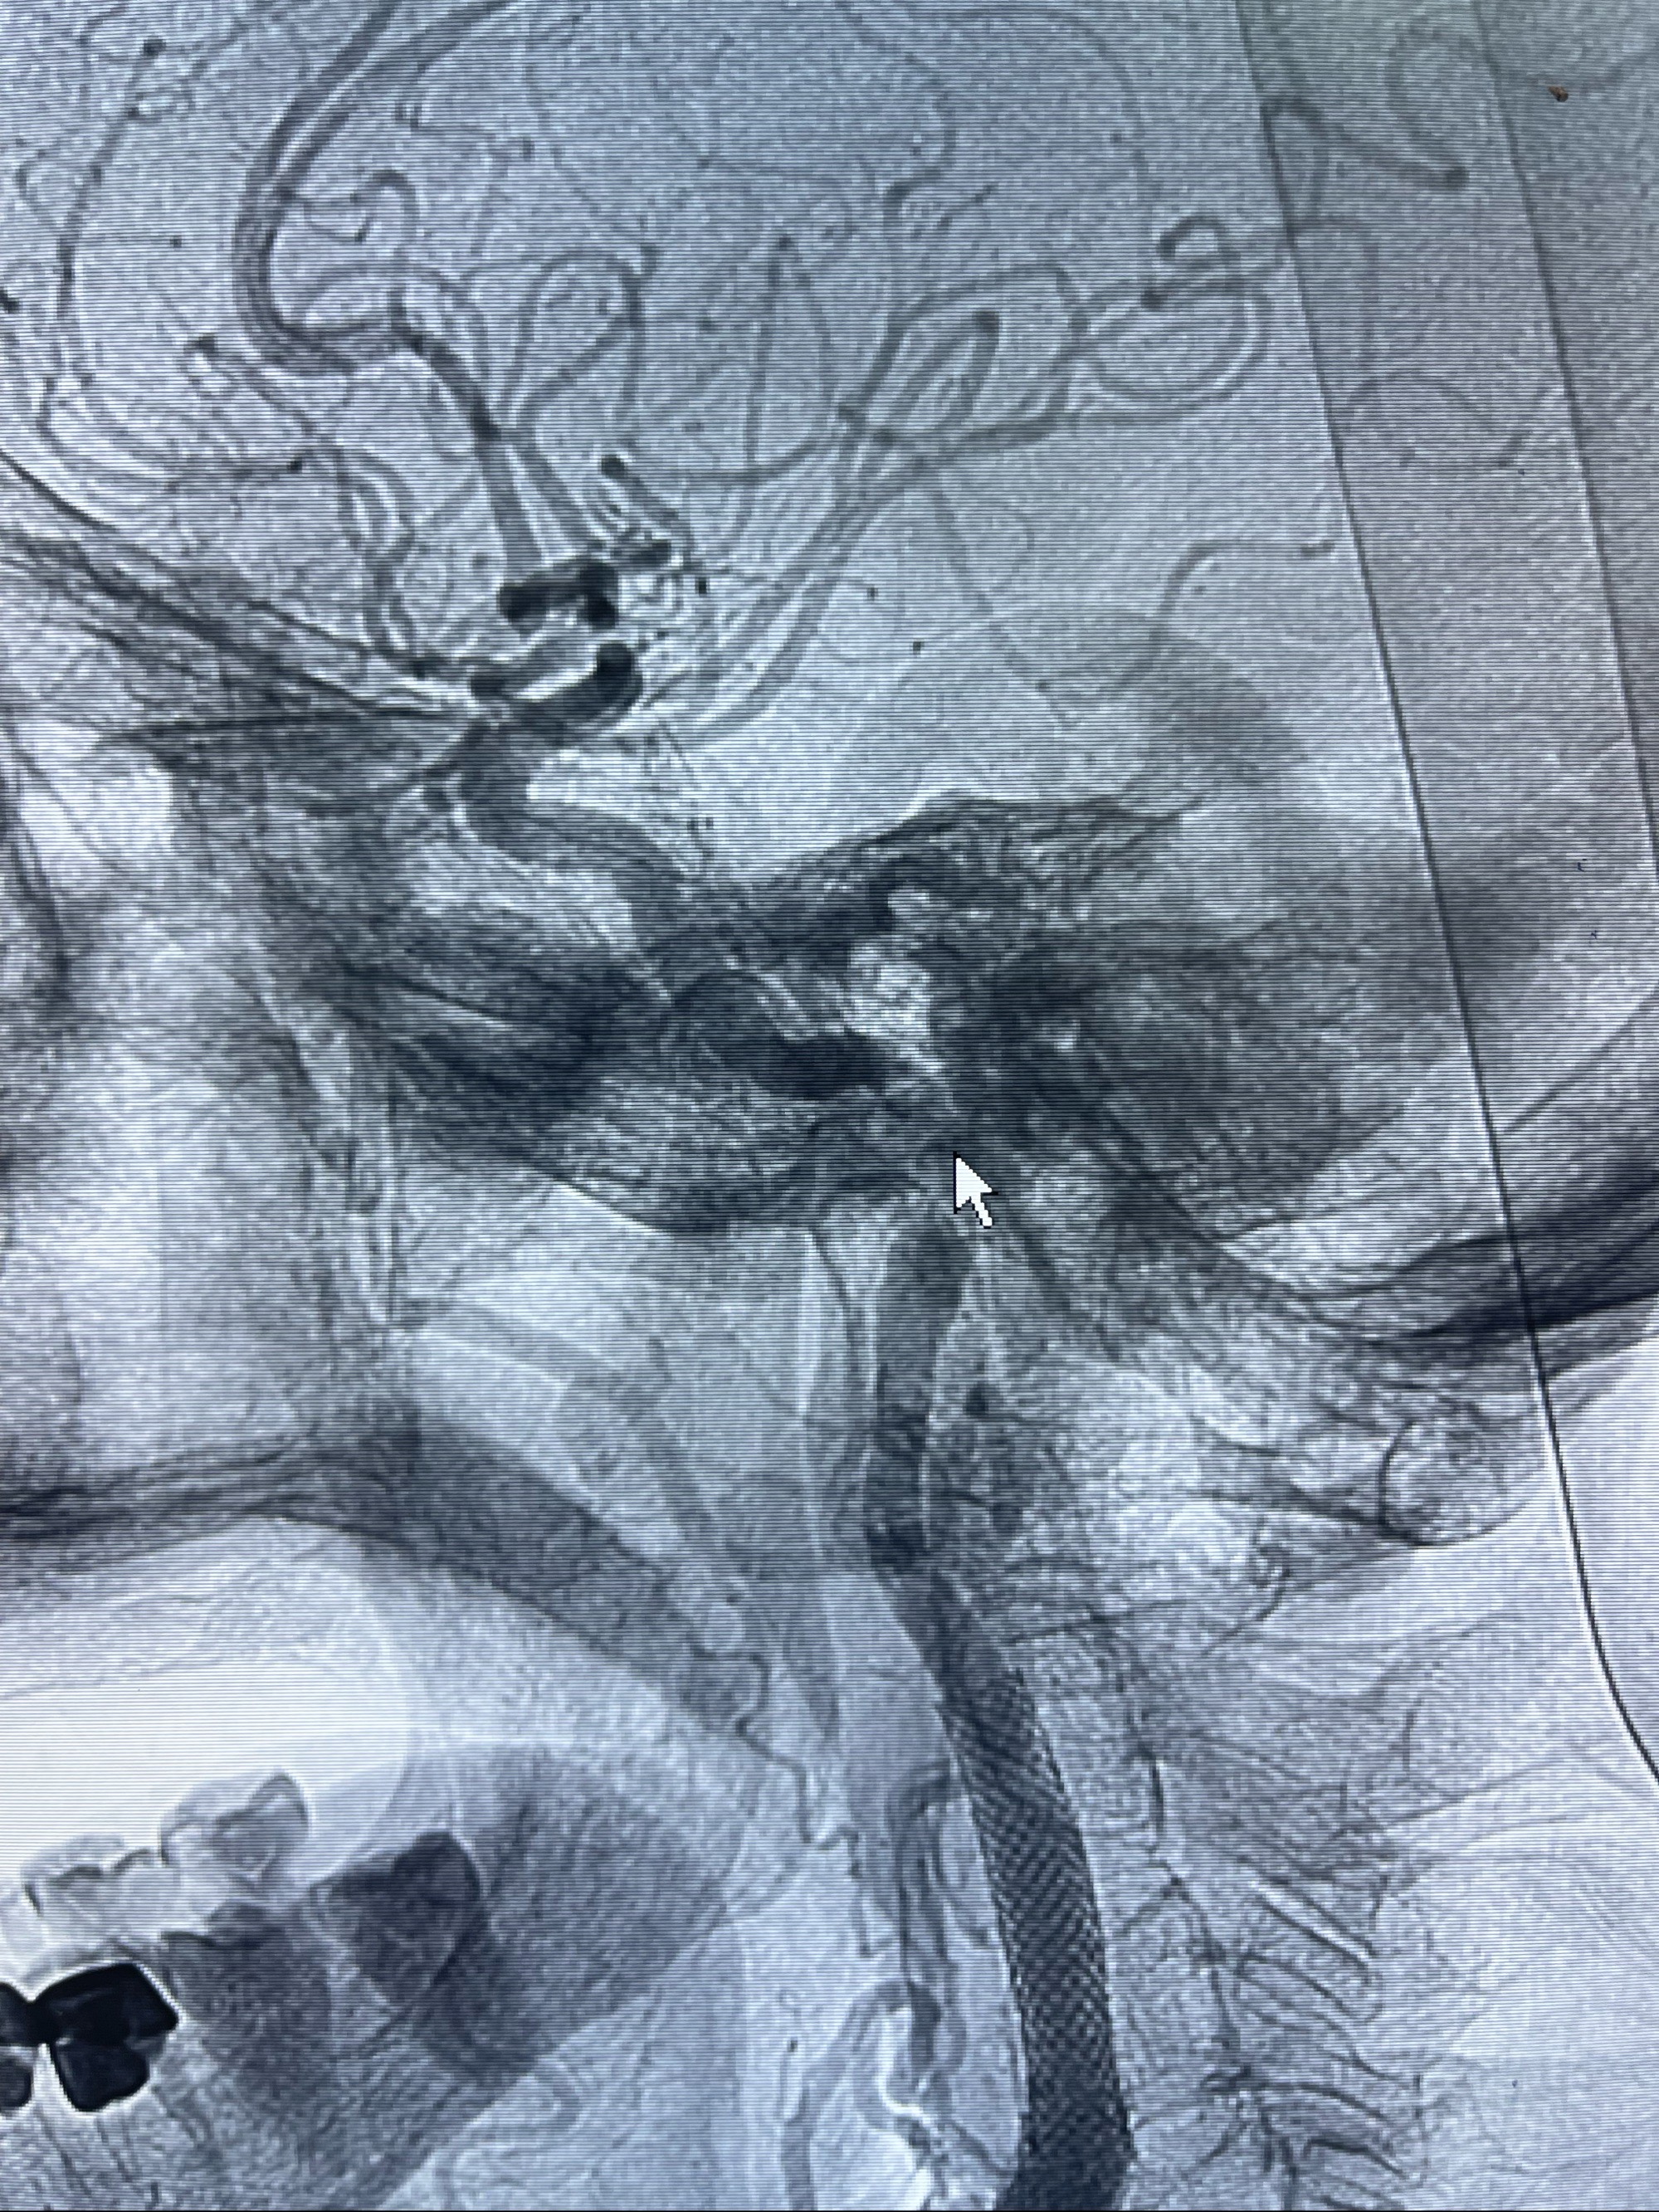

重新行“路径图”,支架导管在微导丝引导下超选择性插入至右侧颈内动脉眼段,4.5-50mmLeo支架释放,远心端位于海绵窦段,近心端位于岩骨段狭窄段以近

即刻造影显示支架贴壁佳

路径图下,5.5-50mmLeo支架导管在微导丝引导下超选择性插入远段Leo支架内

两枚支架部分重叠

多次确认支架位置及打开贴壁情况

支架完全打开,近心端位于原颈动脉支架远心端内